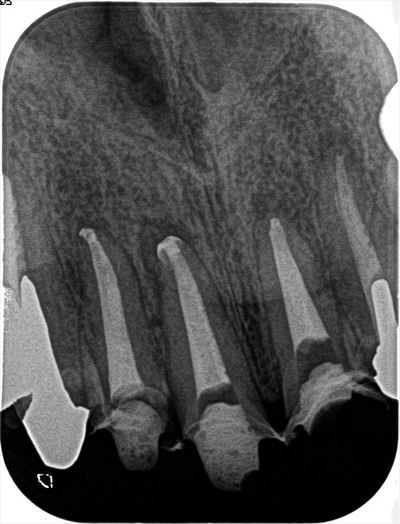

上顎前歯3本の再根管治療・根管充填を行いました。2017.01.20

初診時のレントゲンです。

現時点ではでは画像中央の右上側切歯~左上中切歯までの3本に取り組んでいます。

根尖口は#80以上の比較的大きなサイズになっていました。

前々回に再根管治療を始め、前回の治療時には根尖からの排濃がありましたが

その後、慢性的な根尖部分の違和感も消失傾向にあり、

本日は排濃も落ち着いていたためサーマフィルによる垂直加圧根管充填を行いました。